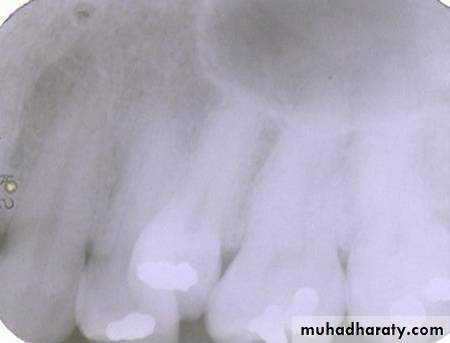

premolar filmThe arrow in the canine film is pointing to the gutta percha in which canal of the maxillary first premolar?

The arrow identifies the lingual canal. The tube head moves mesially from the premolar film to the canine film (beam directed more distally) and the gutta percha indicated by the arrow also moves mesially. (See following slide).

lingual

buccalWhen the tube head is moved mesially, with the beam directed distally, the two canals, which are initially superimposed (premolar periapical above) will separate. The lingual canal (red arrow) will follow the tube head movement and the buccal canal (blue arrow) will move in the opposite direction, as seen on the canine film.